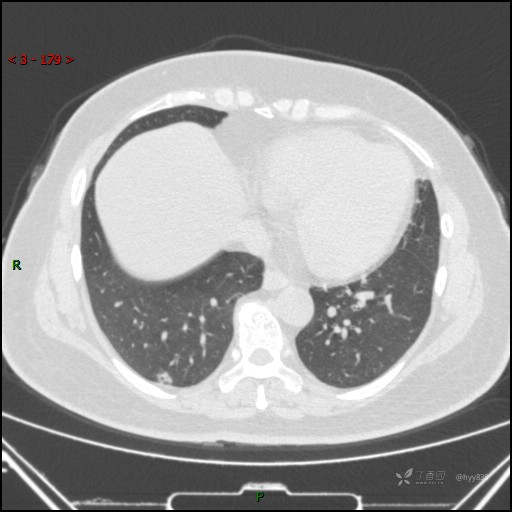

51岁/F,体检发现肺结节,又见“鬼脸”,增强也有特点,请分析---结果公布~

简要病史:体检发现右下肺结节,来我院行进一步增强检查并手术

胸部CT平扫